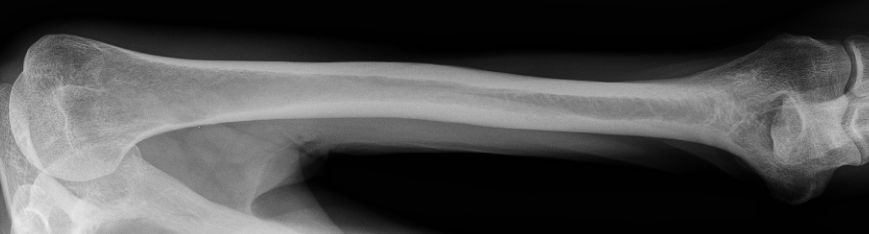

| Ulna | 54-jähriger Mann Adenokarzinom des li OL T4N3M1b. Im Knochenszintigramm fiel eine Mehranreicherung im mittleren Humerusschaft links auf.![]()  | |||